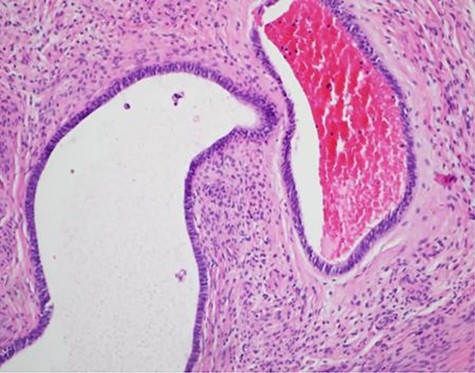

A 52-year-old female presented with complaints of increasing umbilical pain and swelling for a year. She described the pain as intermittent and daily. She denied any aggravating factors. There was no correlation with eating or movement, and she had no relief with Tylenol. Fourteen years ago, she had an umbilical hernia repair at an outside institution, per their documentation; this was done primarily, without mesh. She also had a colonoscopy and upper endoscopy a year prior, which was negative. Her past medical history was remarkable for uterine fibroids. On exam the abdomen was soft and non-distended; the umbilicus was tender to palpation, with no hernia defect palpable. There was no erythema or induration (Fig. 1). At this time the differential included a suture granuloma, benign or malignant mass. A computed tomography (CT) scan of the abdomen and pelvis relieved no hernia but there was an umbilical mass present, a thickened appendiceal tip, abutting a large uterine fibroid (Fig. 2). Tumor markers including carcinoembryonic antigen, carbohydrate antigen (CA) 19-9 and CA 125 were obtained and within normal limits. At this time it was decided that surgical intervention was warranted for increased concerns of malignancy, and a Sister Mary Joseph nodule could not be excluded. The patient was brought to the operating room for a diagnostic laparoscopy. The umbilical mass was excised with a margin of grossly normal tissue (Fig. 3). There were noted to be dense fibrotic adhesions involving the appendix, cecum. The appendix was removed along with a 2-cm ovoid nodule and was sent to pathology along with the umbilical mass. The patient was discharged home the next day without any complications. The pathology revealed an umbilical mass consistent with endometriosis, a pelvic nodule consistent with leiomyoma and a focal area consistent with endometriosis (Fig. 4) She presented to clinic 2 weeks later with no pain or tenderness.